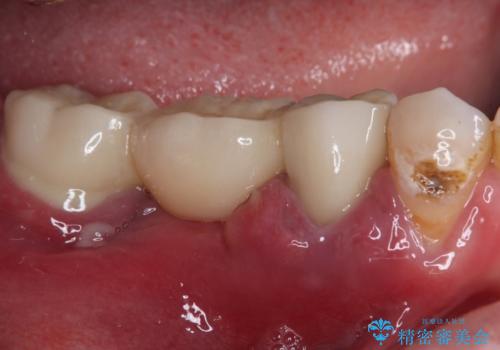

- ブリッジが装着されている奥歯がぐらぐらするとのことで来院された患者様です。

診察を行ったところ、手前の歯は歯根が破折しており、抜歯が必要な状態でした。

左右ともに臼歯部しか咬んでおらず、ブリッジの手前側の歯が破折したことで大きく揺さぶられてしまい、奥側の歯も周辺の歯が著しく吸収し、抜歯が必要な状態でした。

ブリッジの支台歯2本を抜歯し、反対側の咬合負担を軽減するために、通常よりも短い待機時間で2本のインプラントを埋入することとしました。